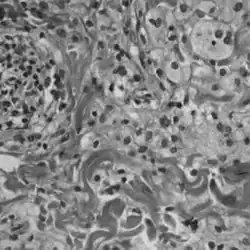

Erdheimova-Chesterova choroba (zkráceně ECD, známá též jako Erdheimův-Chesterův syndrom nebo polyostotická sklerotická histiocytóza) je vzácné onemocnění charakterizované abnormálním zvýšením počtu určitého typu bílých krvinek, tzv. histiocytů, nebo tkáňových makrofágů (technicky se toto onemocnění řadí mezi histiocytózy z non-Langerhansových buněk). Obvykle propuká ve středním věku. Nemoc se projevuje mimo jiné mnohojadernými obrovskými buňkami, zánětlivým infiltrátem lymfocytů a histiocytů v kostní dřeni a generalizovanou sklerózou dlouhých kostí.[1]